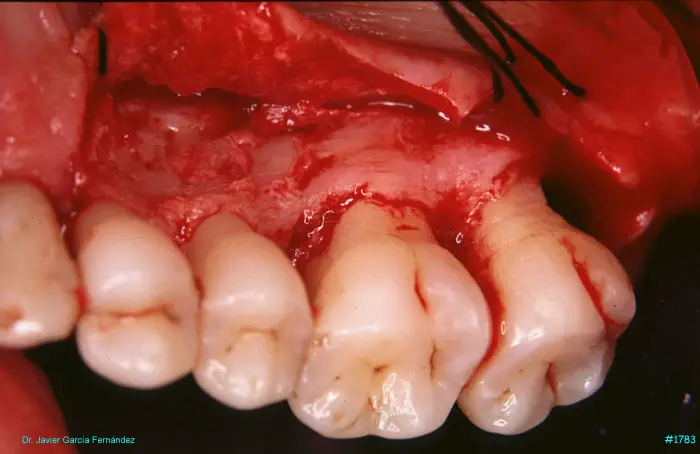

image 51